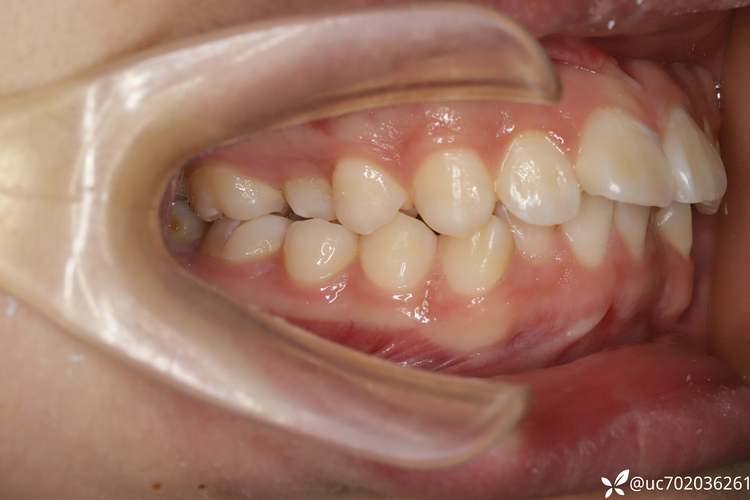

下颌单颗拔牙多适用于轻度至中度牙列拥挤、个别牙扭转或唇倾,以及需要少量间隙调整咬合关系的病例,当下牙列拥挤度在2-4mm之间,且上颌已拔牙需下颌配合时;或存在下颌第二前磨牙严重龋坏、牙根吸收等无法保留的情况,需拔除后利用间隙调整牙列,对于下颌前牙轻微前突但无需大量内收的患者,拔除一颗下颌前磨牙可集中间隙,避免过度拔牙对牙周健康的影响。

正畸拔牙的核心目的是为牙齿移动提供空间,下颌单颗拔牙也不例外,具体目标包括:解除牙列拥挤,通过拔牙间隙将错位牙齿排齐至正常位置;改善前牙覆颌覆盖关系,避免“地包天”或“深覆颌”;调整后牙咬合接触点,使咀嚼力分布均匀;为个别牙(如扭转的中切牙)的扶正提供移动空间,相较于拔除两颗牙,单颗拔牙对牙弓周长的影响较小,更适合间隙需求有限的病例。

下颌单颗拔牙通常选择第一或第二前磨牙(即下颌5号或6号牙),具体需结合牙弓形态、咬合关系及牙齿健康状况决定,下颌第一前磨牙(下5)位于牙弓中段,牙根多为单根(少数双根),牙冠较窄,拔除后对邻牙影响小,且间隙可灵活分配给前牙或后牙;下颌第二前磨牙(下6)牙根可能为双根,牙冠较圆钝,若存在龋坏或形态异常,也可作为拔牙选择,一般优先拔除病变牙或形态异常牙,若牙齿均健康,则通过头影测量分析,选择对咬合功能影响最小的牙位。